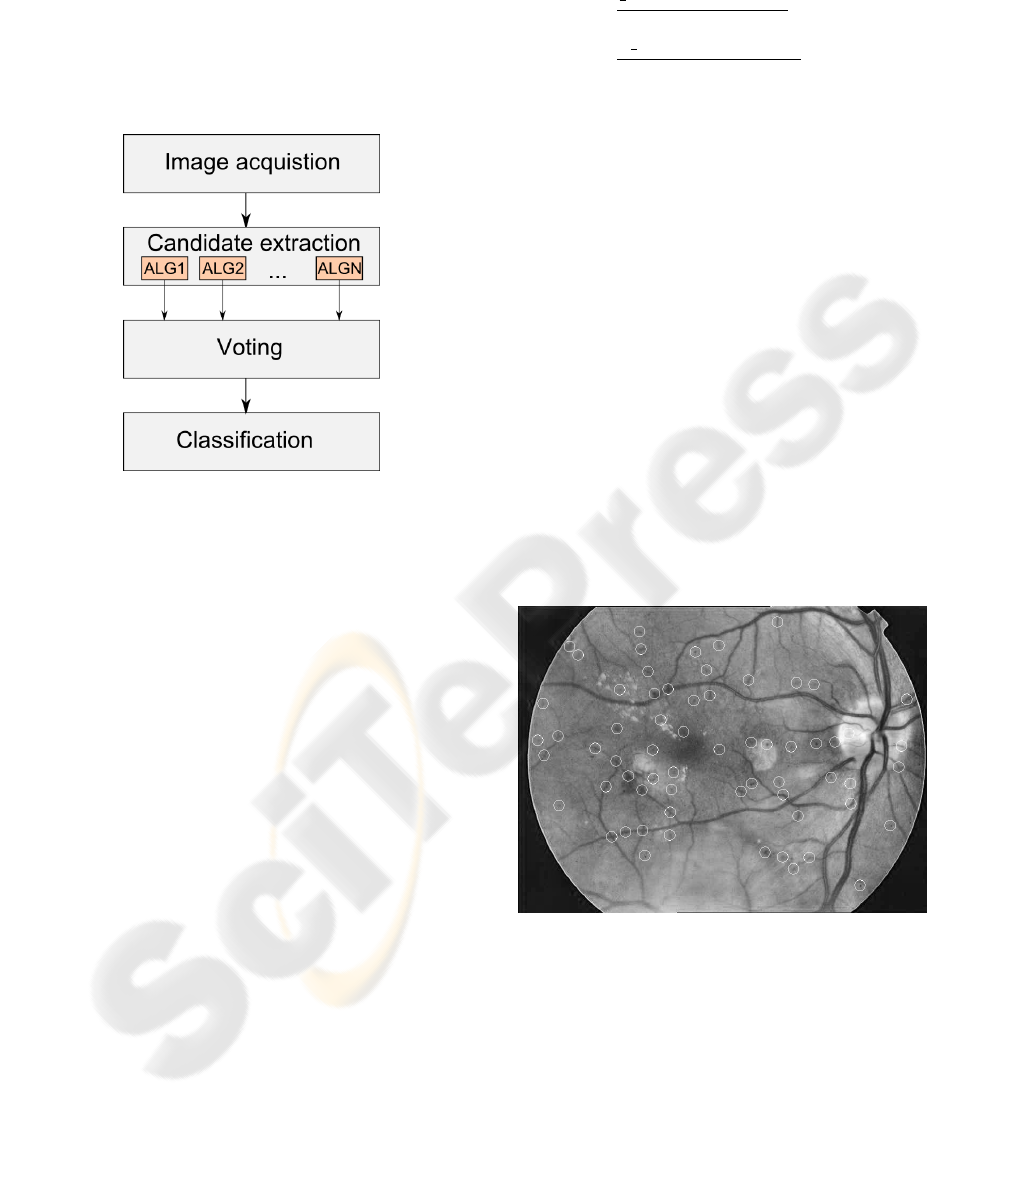

AN OPTIMAL VOTING SCHEME FOR MICROANEURYSM CANDIDATE EXTRACTORS USING SIMULATED

ANNEALING